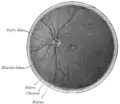

Interior of posterior half of bulb of left eye. The veins are darker in appearance than the arteries. (Central retinal artery visible but not labeled).

Horizontal section of the eyeball.